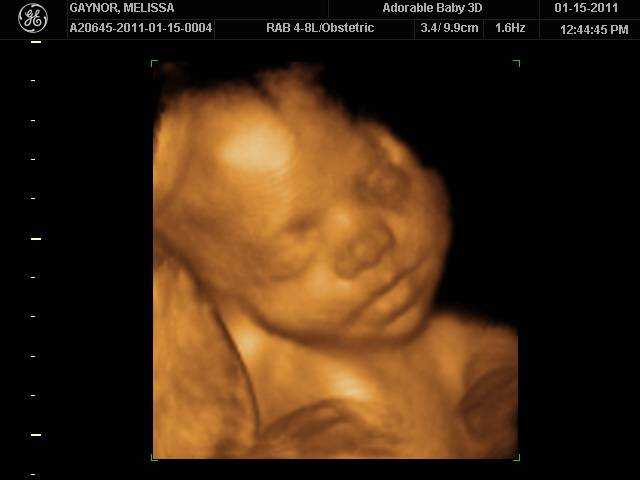

На 29 неделе беременности на головке у малыша уже видны волосики. Сейчас они напоминают скорее пушок. Вместе с этим, пушок, который присутствовал на теле (лануго), исчезает. Уменьшается также количество защитной смазки. С каждым днем увеличивается жировая прокладка и малыш все больше становится похожим на новорожденного. Кожа приобретает светло-розовый оттенок, появляются так называемые младенческие складочки и милая припухлость на щечках.

Внешне, ребенок на 29 неделе беременности выглядит почти так же, как после рождения. Пушок на его коже начинает исчезать, а количество первородной смазки уменьшается к моменту родов. Доля подкожного жира на этой неделе ничтожно мала – около 4%. Однако, по мере роста плода, жировая клетчатка будет активно нарастать, что способствует гладкости кожи.

В период когда развитие беременности составляет 29 недель, то малыш на этом сроке активно накапливает белый жир и набирает в весе. У малютки сейчас можно наблюдать появление пухленьких щечек, здесь в первую очередь будет откладываться жир, но и теряться, что интересно, также здесь. Так задумано было природой для того, чтобы максимально поддержать самую важную способность в первый год жизни крохи — сосание материнской груди.

На 29 неделе беременности малыш выглядит уже почти как новорожденный. Набирать вес и готовить к самостоятельной большой работе легкие — вот основная задача ребенка на последние недели беременности. У малыша на этом сроке уже сформированы зрение, слух, вкус и обоняние, он может различать свет и тьму, но полностью сфокусировать зрение ему еще пока не удается. Умение это в полной мере покорится малышу к моменту появления на свет.

Сейчас плод уже может чувствовать и вкус и запах околоплодных вод; различать свет и звуки; он полностью чувствует настроение и общее состояние матери; может сфокусировать свой взгляд на чем-то одном. Внешне малыш уже начинает походить на новорожденного кроху: его кожный покров светлеет и выравнивается, лануго постепенно начинает сходить, а количество смазки минимизируется. Подкожного жира становится больше и чем ближе к дате родов, тем больше милых складочек образуется на теле ребеночка.

Щечки постепенно округляются вместе с другими частями тела. Так как половые органы сформировались достаточно хорошо, на УЗИ можно уже безошибочно определить пол малыша. С каждым днем организм ребенка начинает функционировать все лучше, превращаясь в гармоничную отлаженную систему. Связки и мышцы продолжают совершенствоваться и крепчать, что ощущается по силе толчков. Учитывая то, что места для кувырканий становится намного меньше, каждый переворот с головы на ноги и наоборот будет четко ощущаться мамочкой.